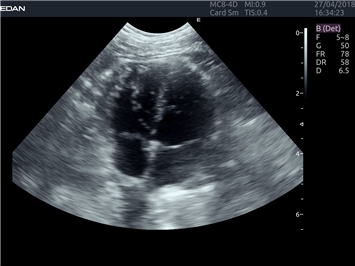

EDAN Acclarix LX4 VET

EDAN Acclarix LX4 VET представляет собой профессиональную ультразвуковую систему, специально разработанную для ветеринарных исследований. Сочетание стабильности, высокой производительности и эффективности делает эту систему идеальным выбором для современной ветеринарной практики.

Области применения:

Система оптимально подходит для:

• Ветеринарных клиник

• Специализированных ветеринарных центров

• Животноводческих комплексов

• Конных клиник

• Научно-исследовательских ветеринарных учреждений